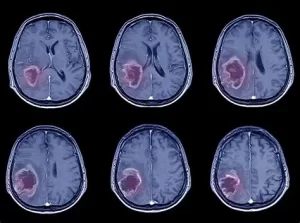

Tendencias recientes en la investigación del cáncer

3. Herramientas de diagnóstico y detección temprana

La tecnología de biomarcadores líquidos, como la biopsia de líquido, está mejorando para detectar mutaciones tumorales en la sangre u otros fluidos, haciendo que los diagnósticos sean menos invasivos y capturando cosas antes, esto significa que podemos intervenir rápidamente y hacer una gran diferencia en cómo resultan las cosas.